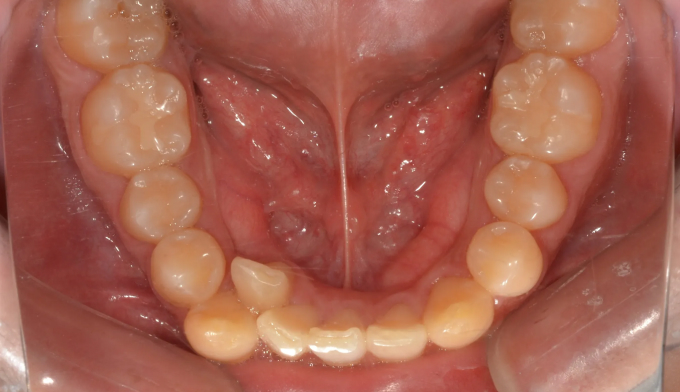

덧니

필요한 공간이 많지 않아도, 입이 많이 나오지 않아도 발치교정을 해야하는 경우들이 종종 있습니다.

비발치교정시 주로 악궁확장이나 치아삭제, 또는 치아 후방이동을 통해 공간을 확보하는데 기존의 악궁이 충분히 넓거나 치아크기가 작은경우, 또는 사랑니가 너무 깊숙히 있어서 발치하기 어려운 경우에는 어쩔 수 없이 작은어금니 발치를 통해 공간을 확보합니다.

교정기간은 총 22개월입니다.